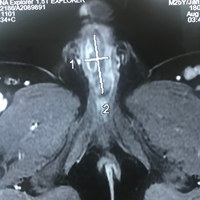

Lấy cuộn cước câu 'ở' trong niệu đạo nam thanh niên 11 năm ảnh 2Chụp MRI cho thấy một dị vật nằm trong niệu đạo bệnh nhân

Anh T.H.N. cho biết hơn 10 năm nay,  thường đi tiểu đau, cảm giác gắt buốt và nước tiểu đục, có lúc tiểu mủ. Vài tháng gần đây, tình trạng đau ngày càng trở nên tồi tệ hơn, người bệnh tiểu khó, da thân dương lở loét và đau đớn. Các kết quả chẩn đoán hình ảnh, cho thấy một vật lạ chưa rõ t đang nằm trong niệu đạo. Để giải quyết nhanh chóng tình trạng bí tiểu và viêm nhiễm vùng sinh dục, các bác sĩ đã tiến hành mở bàng quang ra da để chuyển lưu nước tiểu và điều trị kháng sinh để tình trạng nhiễm trùng được kiểm soát tiến hành phẫu thuật thám sát và tái tạo đường tiểu mới cho người bệnh.